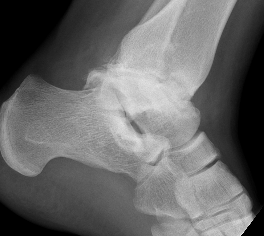

Xray

Talus AVN Post ORIFTalus AVN 1Talus AVN 2

Talus AVNtalus avn